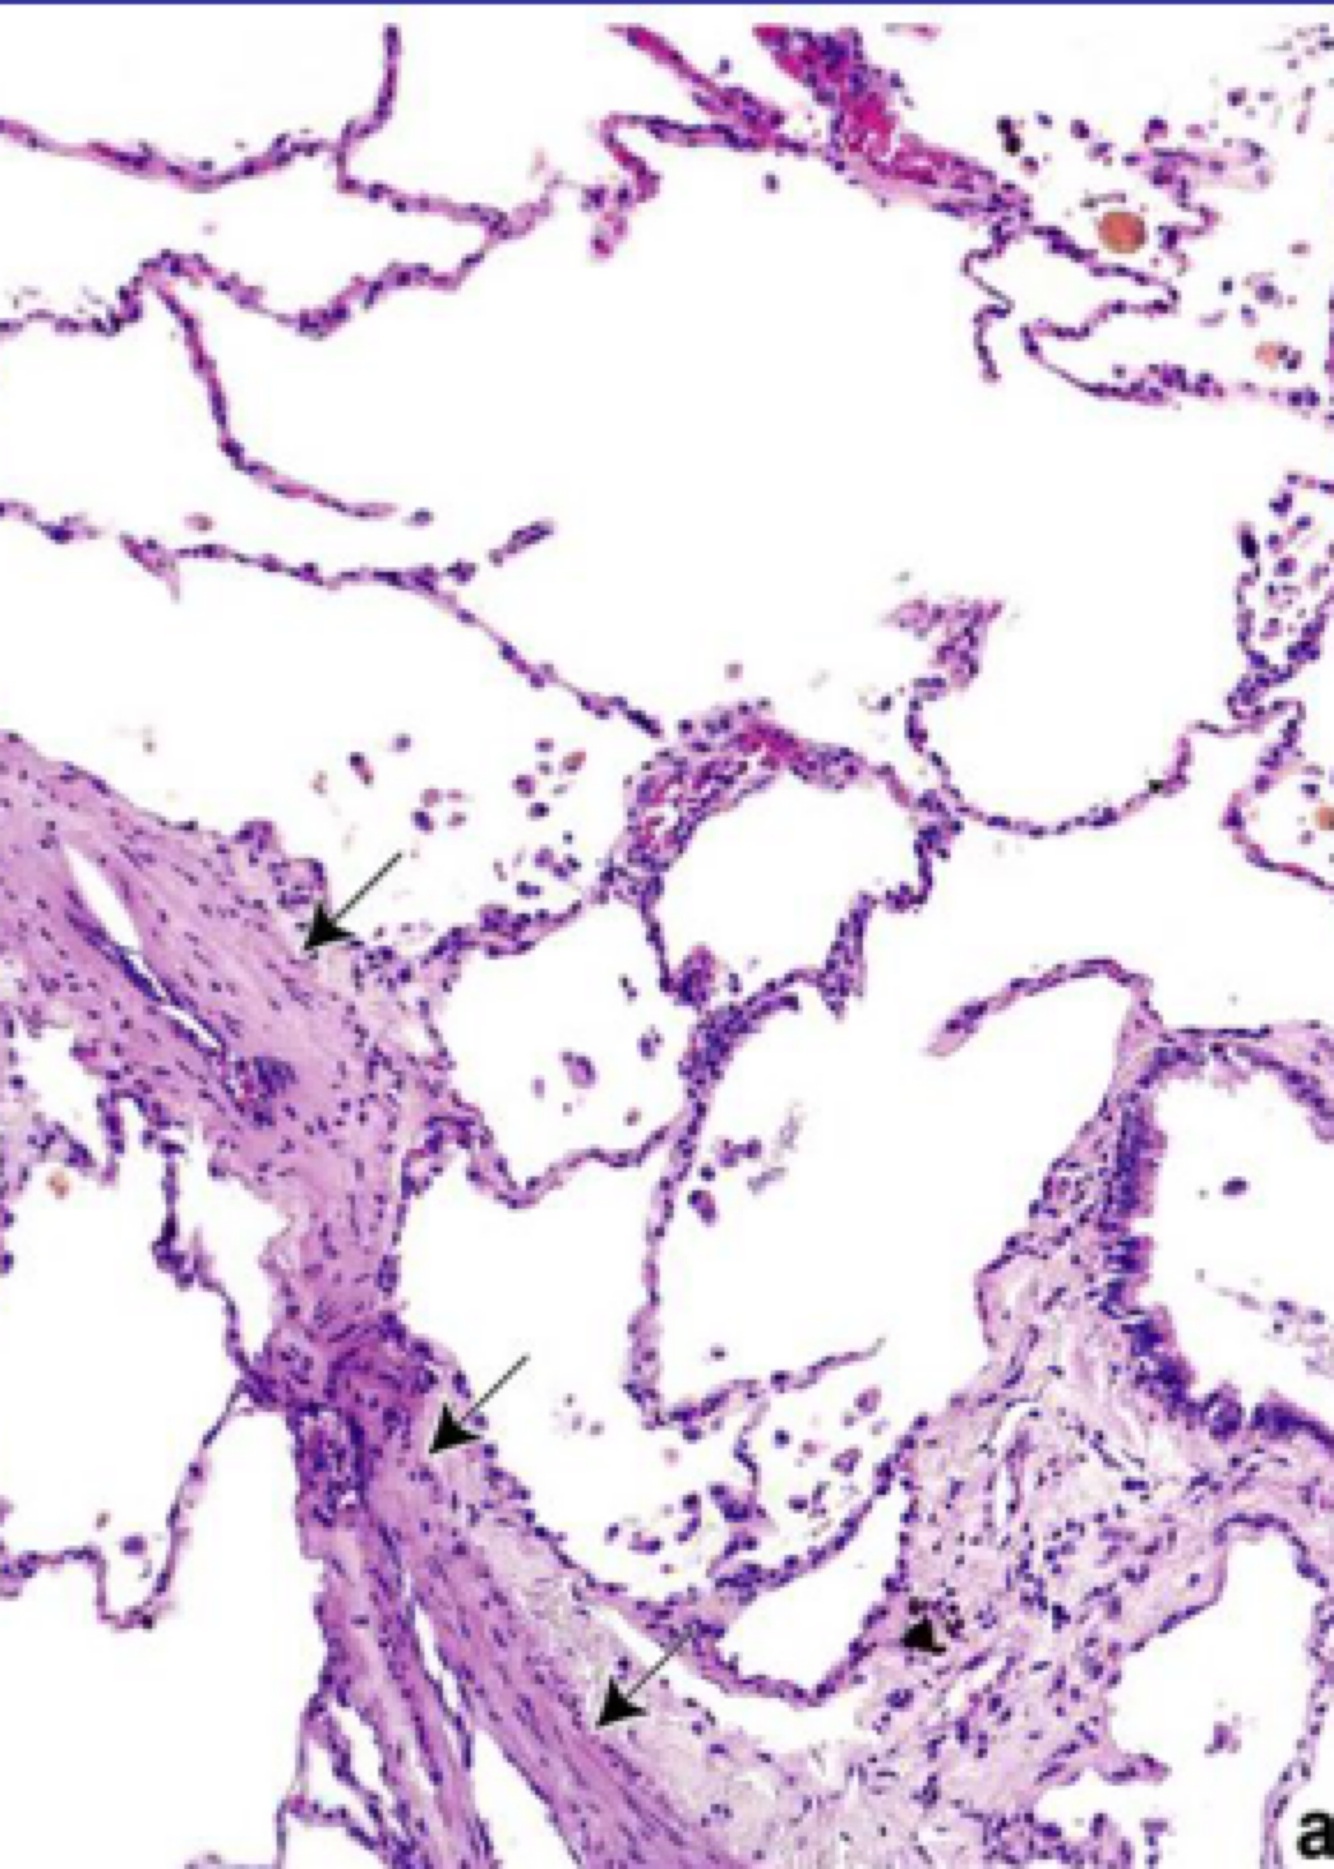

Describe what this histology specimen is showing

Emphysema

Destruction of the alveolar walls which results in bullae, thin alveolar walls

Loss of elastic fibres- pale, stretched-out structures

Inflammatory cells- neutrophils and macrophages